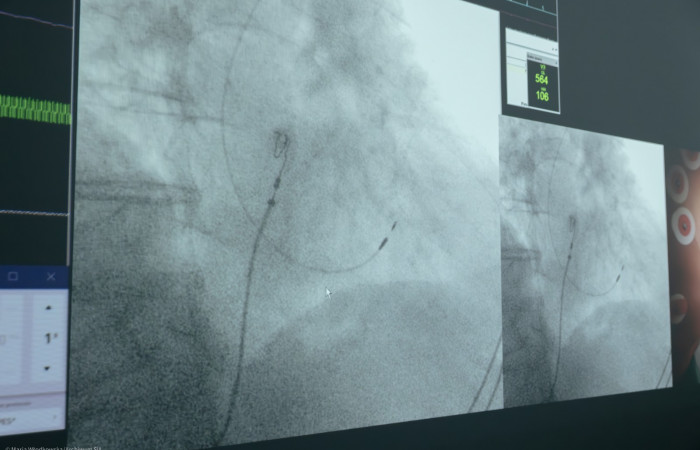

Stymulacja fizjologiczna serca to innowacyjna metoda, w której elektrody precyzyjnie pobudzają układ przewodzący serca - pęczek Hisa lub jego lewą odnogę. Dzięki temu rytm serca przywracany jest w sposób maksymalnie zbliżony do naturalnego. W porównaniu do klasycznych rozruszników serca, terapia ta minimalizuje ryzyko powikłań, poprawia komfort życia pacjentów i pozwala na „naprawę” układu przewodzącego do stanu sprzed wystąpienia choroby, odwzorowując naturalne procesy elektryczne serca.

Część praktyczną PPC poprowadzili: prof. Marek Jastrzębski, dr n. med. Paweł Moskal oraz dr n. med. Grzegorz Kiełbasa. Ich doświadczenie i wiedza pozwoliły uczestnikom warsztatów zobaczyć, jak najnowsze techniki stymulacji fizjologicznej są stosowane w codziennej praktyce klinicznej.